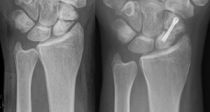

• °ñ´Ù°øÁõ ȯÀÚ 80¸¸¸í¡¦¡°ÇÞºµ ¸¹ÀÌ ÂØ¼¼¿ä¡± °ñ´Ù°øÁõ ȯÀÚ 80¸¸¸í¡¦¡°ÇÞºµ ¸¹ÀÌ ÂØ¼¼¿ä¡± °¡º­¿î Ãæ°Ýµµ °ñÀý·Î À̾îÁú ¼ö ÀÖ´Â °ñ´Ù°øÁõ ȯÀÚ°¡ ¸Å³â Áõ°¡Çϰí ÀÖ´Ù. ±¹¹Î°Ç°­º¸Çè°ø´ÜÀº ±¹³» °ñ´Ù°øÁõ Áø·á ÀοøÀÌ 2008³â 61¸¸4397¸í¿¡¼­ 2013³â 80¸¸7137¸íÀ¸·Î ¸Å³â 5.6%¾¿ Áõ°¡Çß´Ù°í 29ÀÏ ¹àÇû´Ù. °ñ´Ù°øÁõÀº »ÀÀÇ °­µµ°¡ ...